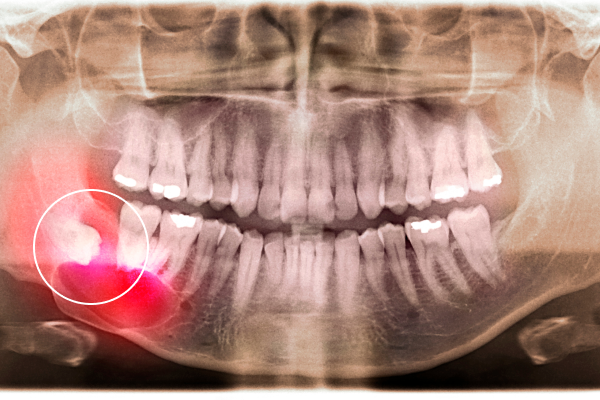

사랑니는 정상적인 기능을 하지 못하면서도 염증과 통증의 원인이 되는 경우가 많아, 상태에 따라 발치가 권장됩니다.

사랑니를 빼야 하는 이유

사랑니는 턱뼈 공간이 부족한 상태에서 맹출되는 경우가 많아 다양한 문제를 반복적으로 유발할 수 있습니다.

잇몸이 완전히 덮이지 않아 염증이 쉽게 생기고 재발합니다.

칫솔질이 어려워 충치가 잘 생기며, 인접 치아까지 손상시킬 수 있습니다.

염증이 반복되면 치조골을 녹여 옆 치아를 흔들리게 만들 수 있습니다.

앞쪽 치아를 밀어 치열을 삐뚤어지게 하는 원인이 되기도 합니다.